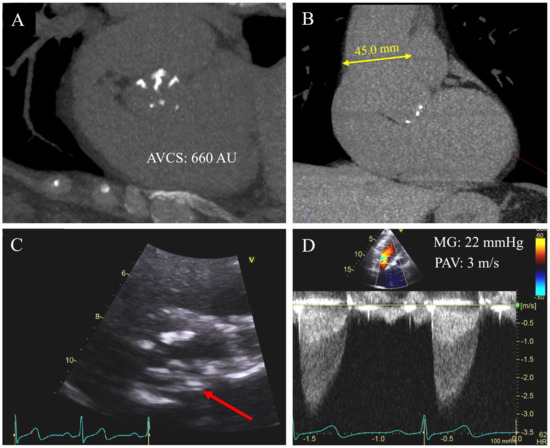

17. AVCS and BAV

BAV is the most common congenital heart disease, with a prevalence as high as 2% in the general population [4]. In these patients, the most common clinical sequela is AS, with up to 37% of patients developing at least moderate AS in their lifetime [3]. Importantly, patients with BAV often develop AS much earlier than those with a tricuspid aortic valve (TAV), presenting up to 15 years earlier [77]. Pathologically, this is thought to be due to higher shear stress on the valve leaflets resulting in earlier fibrosis and calcification [35]. BAV thus leads to preferential calcification of the aortic valve cusps, which progresses to AS and/or aortic regurgitation (Figure 4A,C) [78]. In addition, 20–40% of patients with BAV develop aortic root dilation, associated with an increased risk of aortic dissection (Figure 4B) [3]. Traditionally, patients with severe AS and BAV have been treated with SAVR, however, enhancement in prosthesis design may potentially expand the use of TAVR in BAV. To date, there has been limitation in the use of TAVR in these patients due to the complex anatomy leading to increased post-procedure complications including paravalvular leak and aortic root rupture, which are associated with increased mortality [3,79]. As such, evaluation of AV calcification in BAV patients may allow for better risk stratification and decision-making in the pre-intervention stage.

Figure 4.

A 62-year-old asymptomatic female sent for coronary artery calcium (CAC) score for risk stratification for statin therapy. The CAC score was 0, but significant aortic valve calcification was identified (A). AVCS was quantified as 660 AU. She was also incidentally noted to have mid ascending aorta dilation with diameter of 45 mm (B). Subsequent echocardiogram for further evaluation confirmed a bicuspid aortic valve with raphe between the left and non-coronary cusp, demonstrated by arrow (C), and overall moderate aortic stenosis with mean gradient (MG) of 22 mmHg and peak aortic velocity (PAV) of 3 m/s (D).